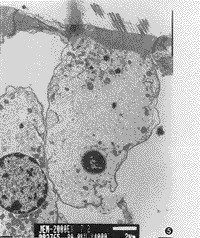

3.耳蜗铺片及透射电镜所见:耳蜗铺片显示GM组用药后3排外毛细胞损伤明显比GM+DFO组重(图2,3),且从顶回至底回逐渐加重,外毛细胞损伤较内毛细胞重。透射电镜见GM组耳蜗毛细胞胞浆细胞器减少,呈空泡变性(图4);GM+DFO组则显示损伤较轻,线粒体完整,出现一些多泡体结构(图5)。GM组还可见耳蜗传入神经突触线粒体空化,血管纹边缘细胞突起中的少数线粒体亦出现嵴减少、空化。DFO组与对照组用药前后耳蜗铺片及透射电镜改变不明显。

图4 透射电镜观察GM组毛细胞胞浆稀疏呈空泡变性,胞核浓缩。×6000

图5 透射电镜观察GM+DFO组毛细胞胞浆丰富,有多个多泡体形成。×4000